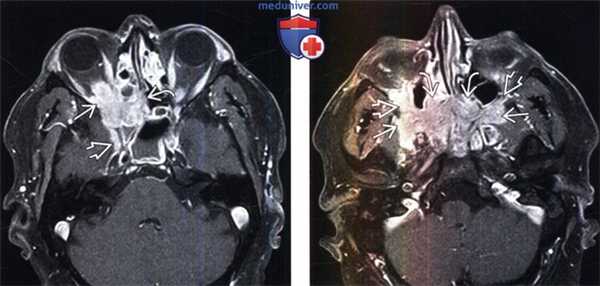

(Слева) У пожилой женщины с нейрооптикопатией при МРТ Т1ВИ FS c Ky в аксиальной проекции внутри мышечного конуса визуализируется объемное образование, окружающее влагалище зрительного нерва. На основании клинических проявлений был выставлен предположительный диагноз менингиома.

(Справа) У этой же пациентки два года спустя при аксиальной МРТ Т1ВИ FS с КУ наблюдается почти полное спонтанное разрешение образования внутри мышечного конуса, вдоль влагалища зрительного нерва видна лишь узкая минимально контрастная полоска. Предположительный диагноз: идиопатическое воспаление глазницы.

(Слева) При МРТ Т1ВИ FS c КУ в аксиальной проекции у пациента с болезненным экзофтальмом определяется объемное образование глазницы, поражающее наружную прямую мышцу и ткани внутри мышечного конуса. Обратите внимание на распространение идиопатического воспаления через верхнюю глазничную щель в переднюю часть кавернозного синуса.

(Справа) При МРТ Т1ВИ FS с КУ в корональной проекции у этого же пациента видно, что объемное образование распространяется в полость черепа и прорастает в левый кавернозный синус. Распространение идиопатического воспаления глазницы в кавернозный синус - наиболее часто встречающаяся локализация внеглазничного поражения.

(Слева) При MPT Т1ВИ FS с КУ в аксиальной проекции определяется обширный контрастный идиопатический воспалительный псевдотумор, инфильтрирующий верхушку глазницы, решетчатый лабиринт и круглое отверстие.

(Справа) При МРТ T1ВИ с КУ в аксиальной проекции (срез проходит ниже) у этого же пациента определяется двусторонний псевдотумор крылонебной ямки, непосредственно соединенный с идиопатическим воспалительным псевдотумором полости носа. Также поражены обе нижние глазничные щели. Обширные идиопатические воспалительные псевдотуморы глаз-ниц/внеглазничной локализации зачастую трудно поддаются лечению стероидами.